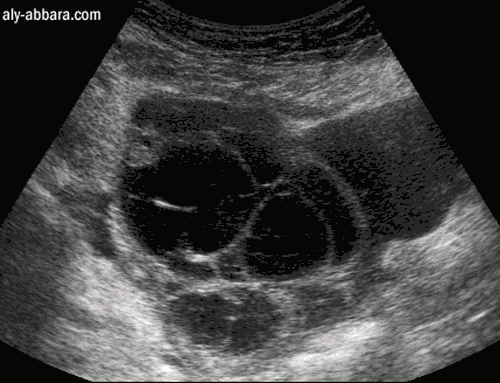

Volumineux kyste mucoïde de l'ovaire

(cystadénome mucineux bénin)